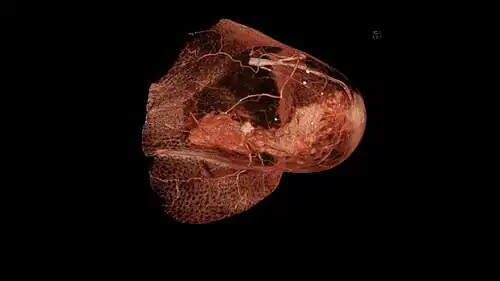

Ein lange Zeit unbehandeltes Mammakarzinom oder ein nicht kontrollierbares lokales Tumorrezidiv kann sich lymphangitisch oder subkutan infiltrierend soweit ausdehnen, dass die gesamte Brustwand panzerförmig ummauert erscheint; dieser Zustand wird als Cancer en cuirasse (Panzerkrebs) bezeichnet.[100]